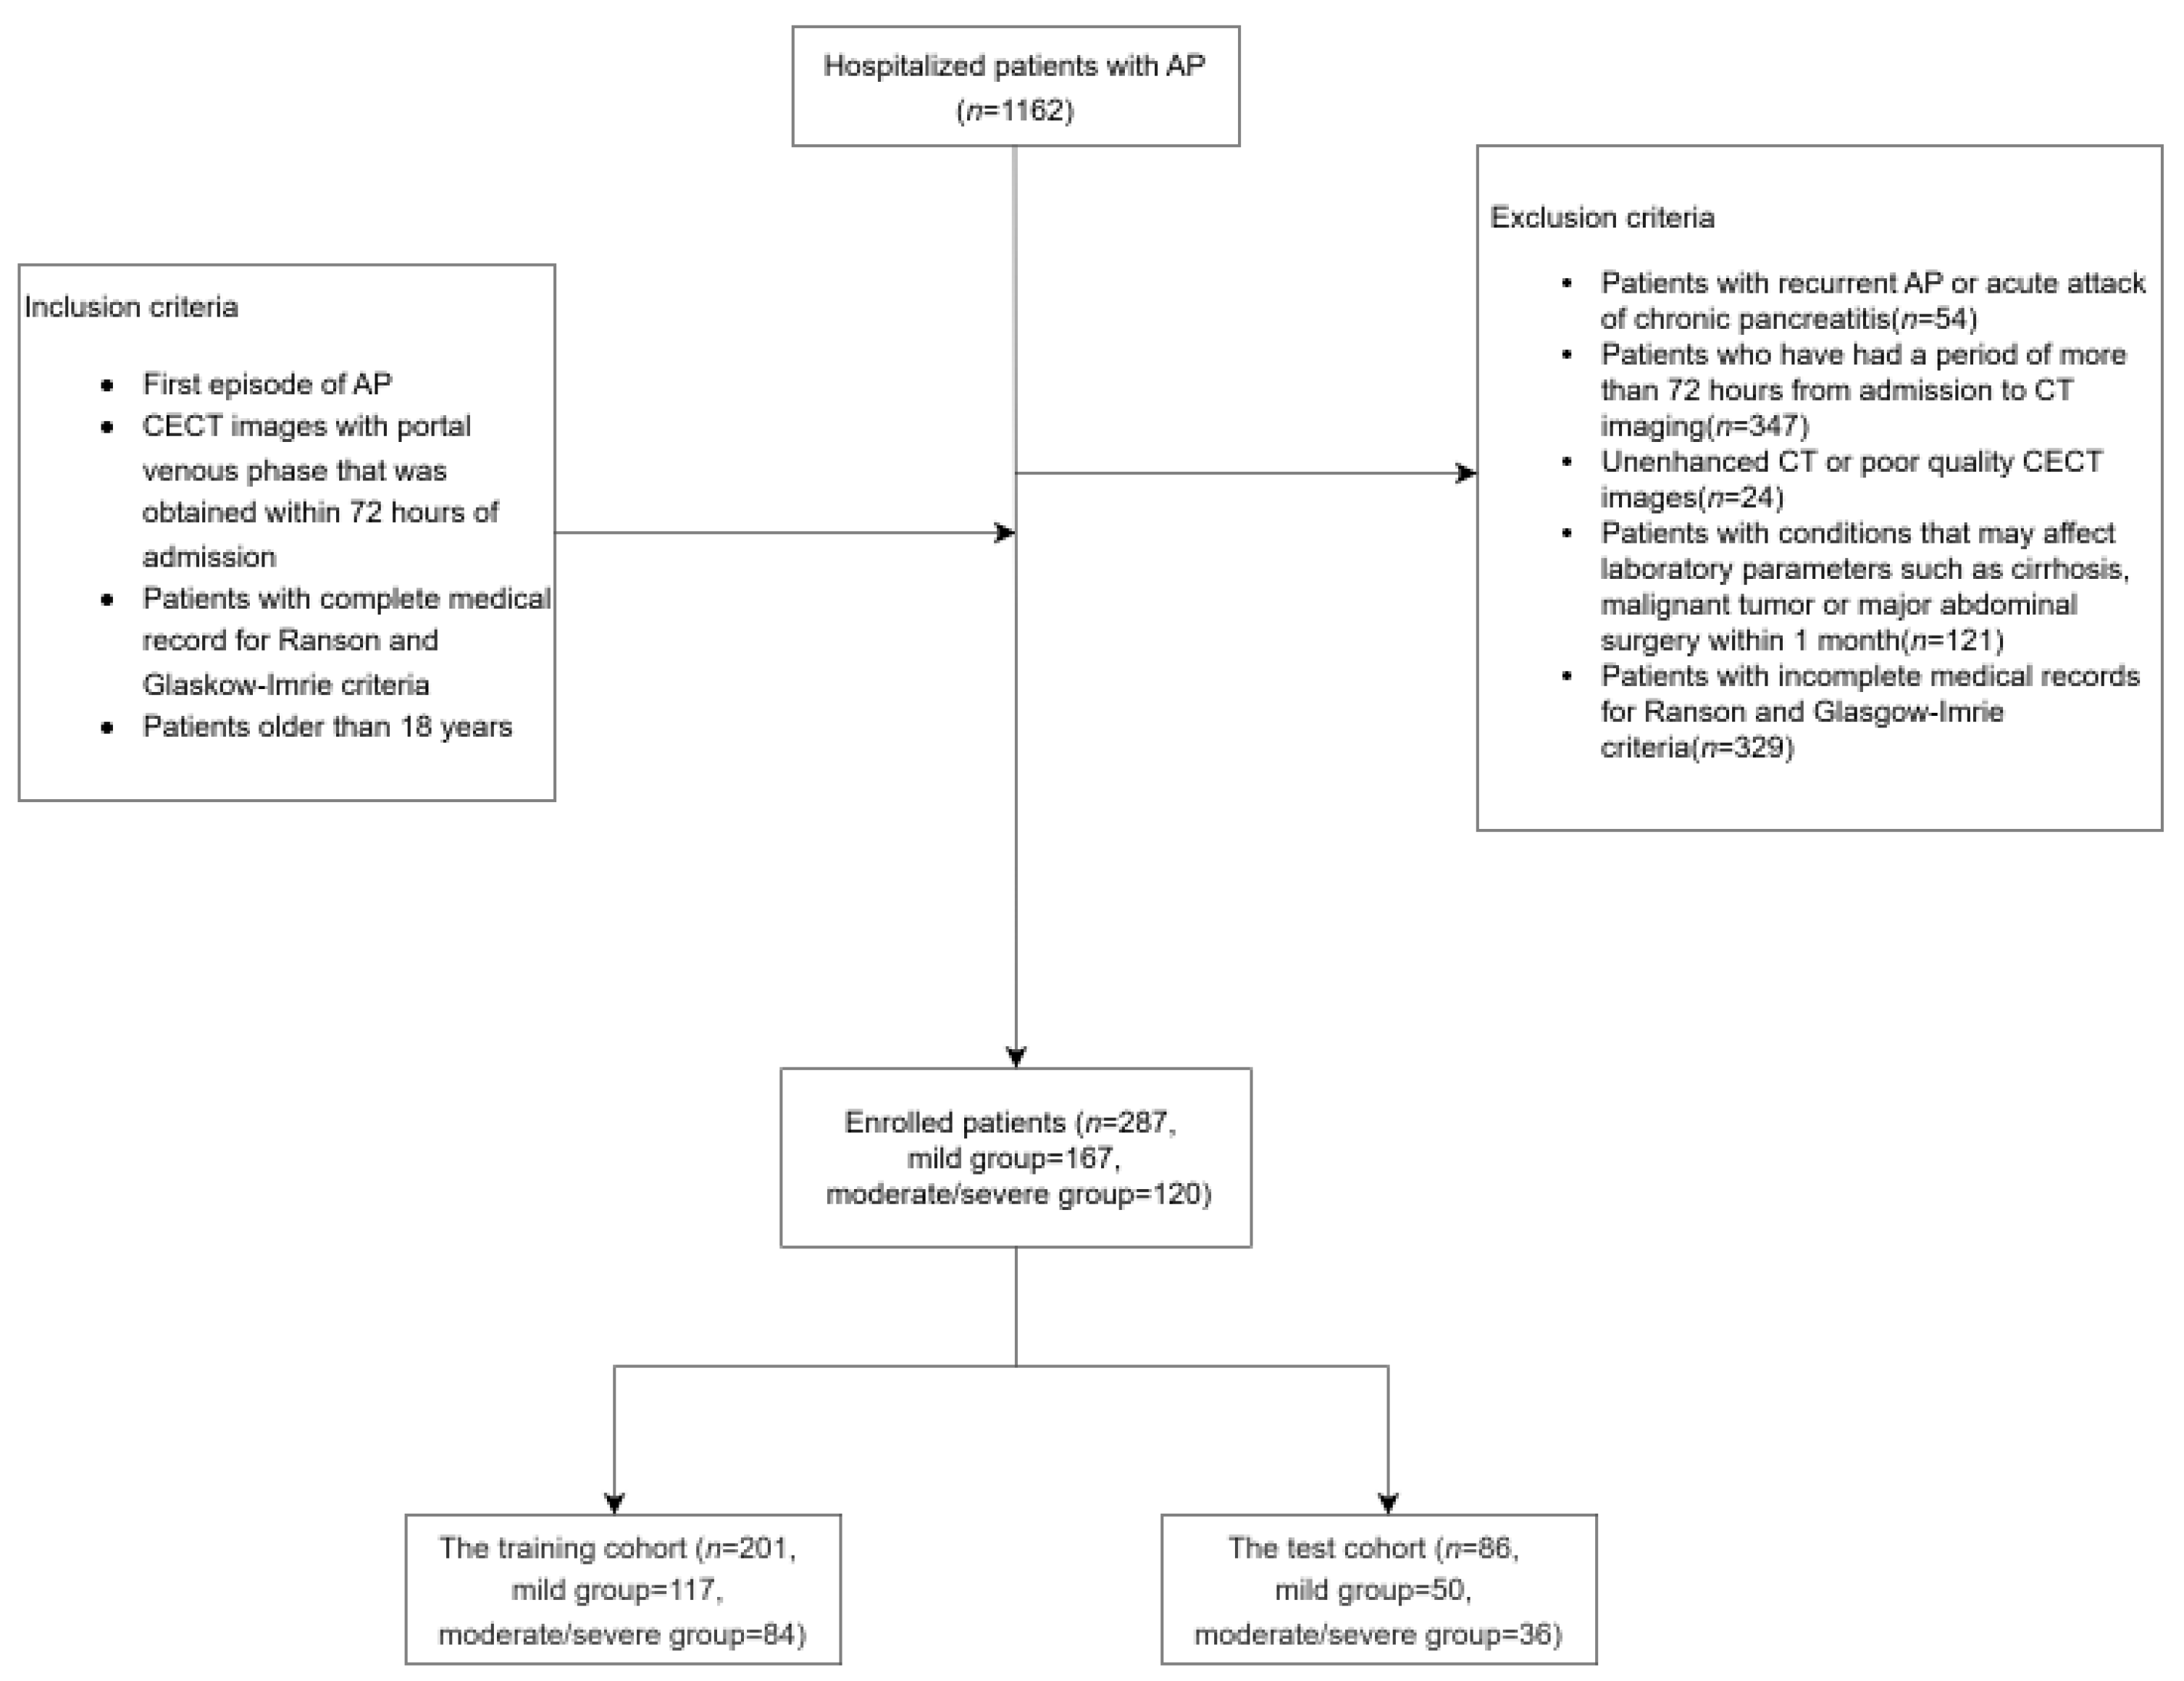

2. Materials and Methods

2.1. Data Collection

- Patients aged ≥ 18 years.

- First episode of AP.

- CECT with portal venous phase acquired within 72 h of admission.

- Complete medical records for Ranson and Glasgow-Imrie scoring.

- Incomplete medical records for Ranson and Glasgow-Imrie scoring.

- History of recurrent AP or acute exacerbations of chronic pancreatitis.

- Conditions potentially affecting laboratory results, including cirrhosis, malignancy, or major abdominal surgery within the past month.

- CECT was performed more than 72 h after admission.

- Unenhanced or poor-quality CECT images.